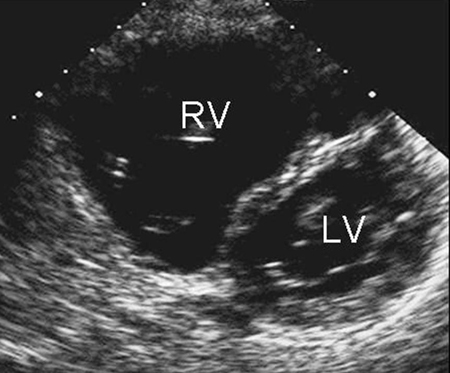

[Figure caption and citation for the preceding image starts]: Imagem de ecocardiografia apical de 4 câmaras revelando dilatação do ventrículo direito em um paciente com defeito do septo atrial (DSA). (AD) átrio direito; (VD) ventrículo direito; (VE) ventrículo esquerdoImagem cedida por Patrick W. O'Leary, MD [Citation ends].